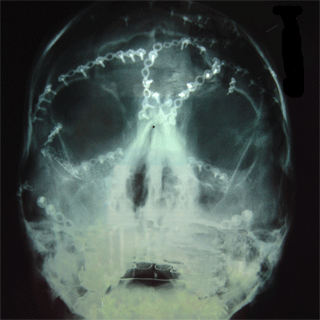

A close up of some of the metal screws in my face. There

is a lot of 'glare' around the mouth because of all of the metal in place.

It effetcs the x-ray, apparently.